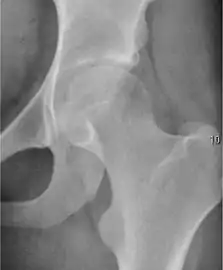

- Osteoarthritis

In adults, one of the main indications for radiographs is the detection of osteoarthritic changes (Figure 1(e)). Nevertheless, radiographs usually detect advanced osteoarthritis that can be graded according to the Tönnis classifications. The grading system ranges from 0 to 3, where 0 shows no sign of osteoarthritis. Intermediate grade 1 shows mild sclerosis of the head and acetabulum, slight joint space narrowing, and marginal osteophyte lipping. Grade 2 presents with small cysts in the femoral head or acetabulum, moderate joint space narrowing, and moderate loss of sphericity of the femoral head. Grade 3 is the severest form of osteoarthritis, which manifests as severe narrowing of the joint space, large subchondral cyst with productive bone changes that may lead to deformity of the bone components of the joint, while secondary osteoarthritis due to calcium pyrophosphate deposition can be diagnosed when calcification of hyaline cartilage and fibrocartilage is detected.[1]

There are other pathological conditions that can affect the hip joint and radiographs help to make the appropriate diagnosis. Acute bacterial septic arthritis can be diagnosed by radiographs when a fast regional osteoporosis and destructive monoarticular process develops (Figure 1(f)). In case of tuberculous or brucella arthritis it is manifested as a slow progressive process, and diagnosis may be delayed.[1]